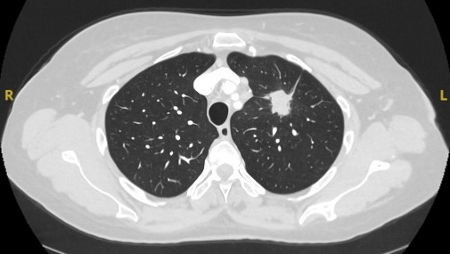

Tomografia computadorizada (TC) mostrando um pequeno nódulo no lobo superior esquerdo com margens lisas, posteriormente considerado uma metástase colorretal solitária na ressecção

Do acervo de Dr. George Tsaknis, MD, PhD, FRCP (Londres), MRQA, MAcadMEd, PGCert; usado com permissão